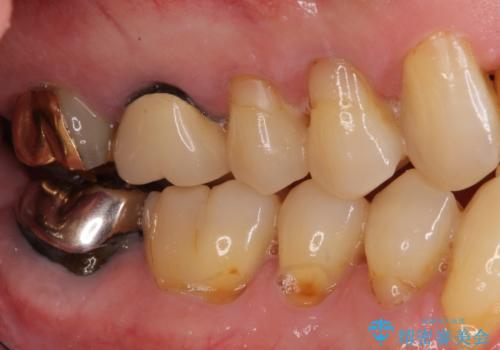

- 上の前歯が痛むとのことで来院された患者様です。

検査を行ったところ、前歯1本は周辺の骨が失われており、抜歯が必要でした。

上顎の奥歯は全体的に歯周ポケットが散見され出血が認められたため、歯周外科処置を行うこととしました。